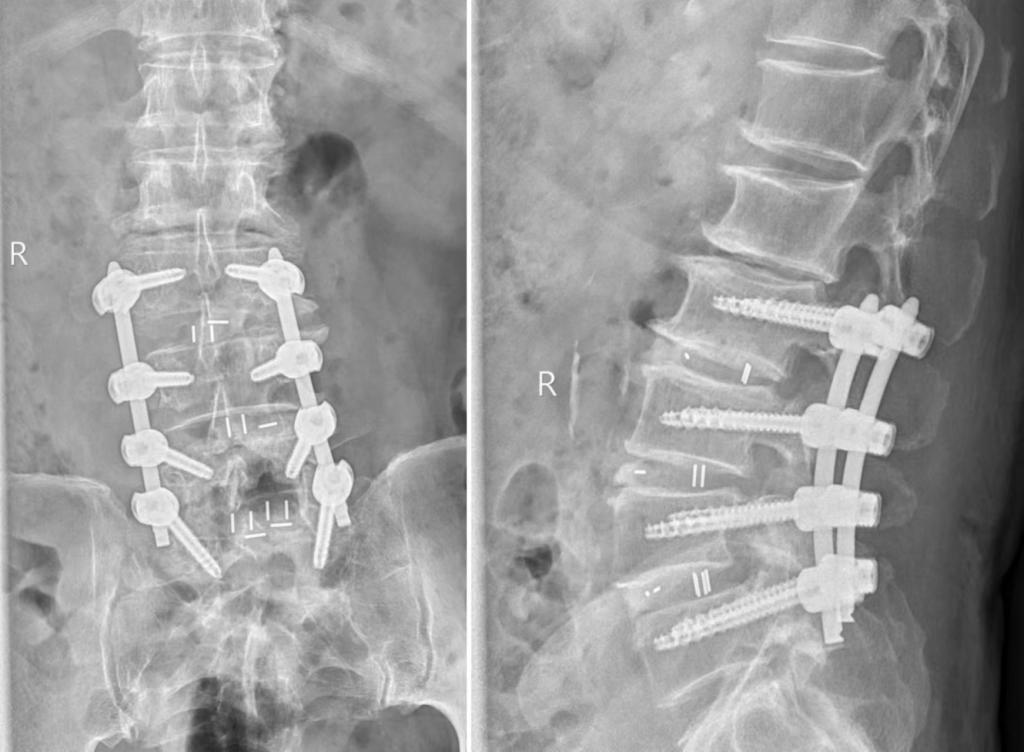

术后腰椎X线片

73岁的男性患者因“长期腰痛伴双下肢无力10余年”就诊于我医院运动医学科脊柱微创门诊。经过详细检查和评估后发现其存在腰3~骶1(L3-S1)多节段椎间盘突出、腰椎滑脱、椎管狭窄,退变性侧弯等问题,面对如此复杂的病情,柏传毅教授决定采用多窗口经肌间隙入路技术进行微创手术治疗,同时完成椎间盘减压,椎间隙固定融合,腰椎不稳定及侧凸矫形。在小通道多窗口经多个肌间隙,分别对3个节段病变椎间盘减压,椎间隙融合固定,并对脊柱的侧弯和滑脱矫形,充分体现了微创手术效果好、创伤小、康复快的特点。较以往观念,多节段脊柱无法做微创的观念,在熟练掌握传统微创技术下提出了多窗口经肌间隙入路技术,可以完成3节段及以上的椎间盘减压,椎间隙固定融合,脊柱不稳定及侧凸矫形等手术,对于高龄患者,多节段腰椎疾病及现在血源短缺的医疗环境下相对于传统手术有很大的优势。

骨科中心运动医学病区开展了脊柱内镜下椎间盘突出髓核摘除和椎管狭窄扩大术,通道下微创侧后路椎间盘突出髓核摘除椎间融合固定术,机器人辅助下腰椎减压固定融合手术等一系列脊柱微创手术,患者取得良好的临床效果,此次开展的多窗口经肌间隙入路腰椎管减压、椎间隙固定融合,腰椎不稳定及侧凸矫形,显示运动医学病区脊柱微创技术可以为多节段椎间盘突出、椎管狭窄、退变畸形的复杂患者提供微创的治疗,并获得良好的效果。